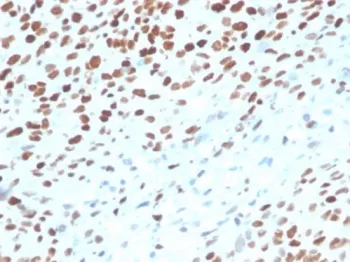

p53 Recombinant Antibody / TP53

Recognizes a 53kDa protein, which is identified as p53 suppressor gene product. It reacts with the mutant as well as the wild form of p53 protein. p53 is a tumor suppressor gene expressed in a wide variety of tissue types and is involved in regulating cell growth, replication, and apoptosis. It binds to MDM2, SV40 T antigen and human papilloma virus E6 protein. Positive nuclear staining with p53 antibody has been reported to be a negative prognostic factor in breast carcinoma, lung carcinoma, colorectal, and urothelial carcinoma. Anti-p53 positivity has also been used to differentiate uterine serous carcinoma from endometrioid carcinoma as well as to detect intratubular germ cell neoplasia. Mutations involving p53 are found in a wide variety of malignant tumors, including breast, ovarian, bladder, colon, lung, and melanoma.UniProt: